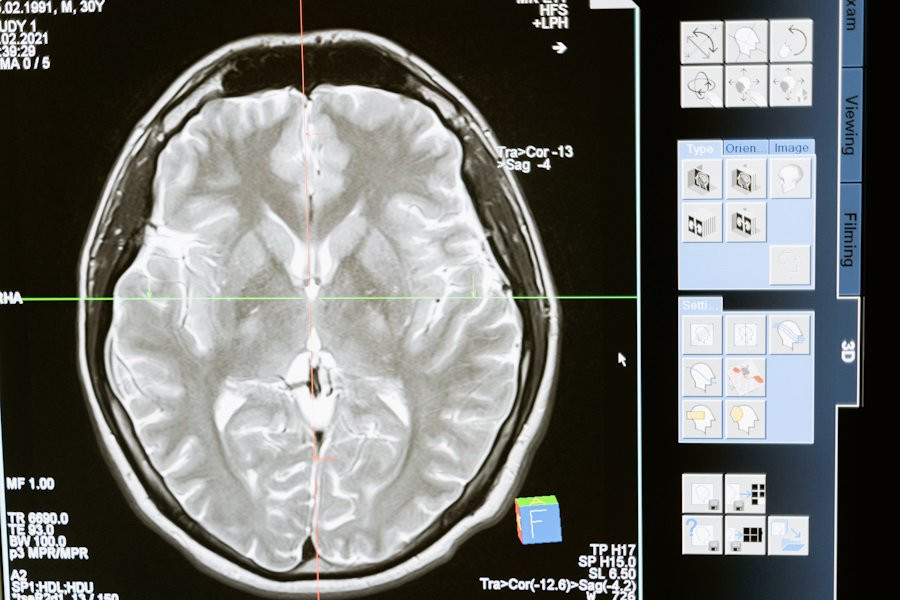

Фото из открытых источников

Головной мозг защищен от внешних воздействий с помощью особого барьера — гематоэнцефалического, который не пропускает посторонние вещества. Это сильно затрудняет доставку лекарств, особенно при лечении таких сложных заболеваний, как глиобластома — самый агрессивный вид первичного рака мозга. Но, благодаря работе ученых под руководством профессора Беренда Снейдера, может появиться новый подход к лечению этого заболевания.